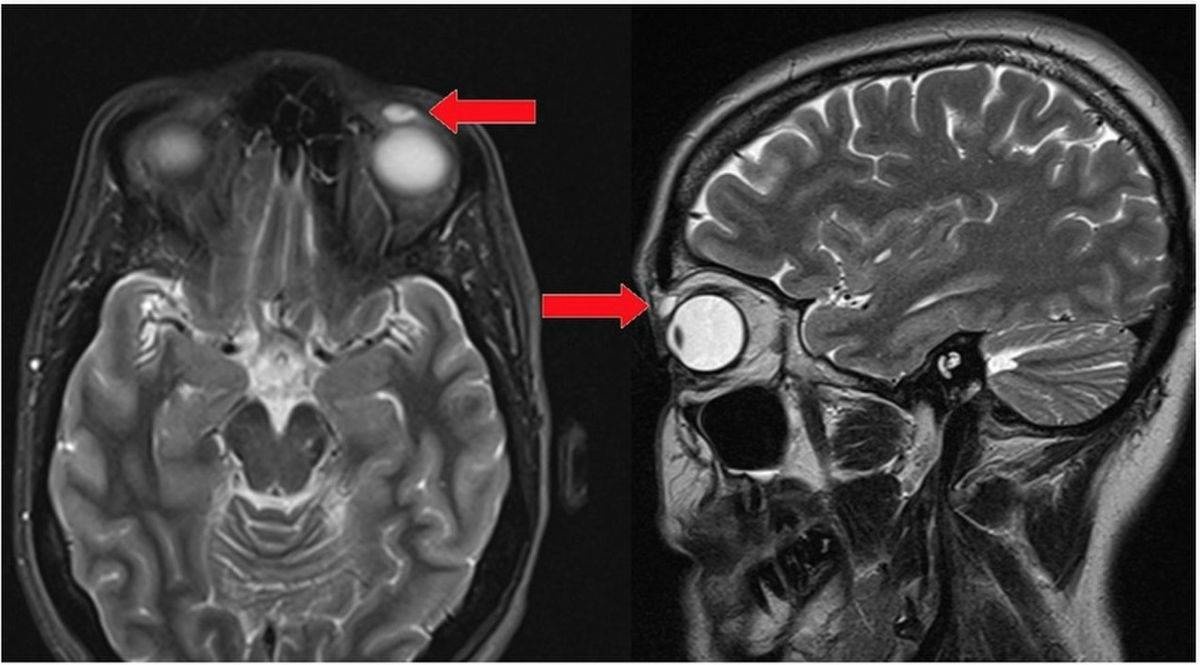

まぶたの裏にコンタクト27枚収納事件

レス10番の画像1

レス10番の画像2

こいつでも生きてるんだし大丈夫だよね?

>>10

これ外科手術ならイッチも手術になるんかね?

枚数違うとは言えたぶん起こったことは同じやろ